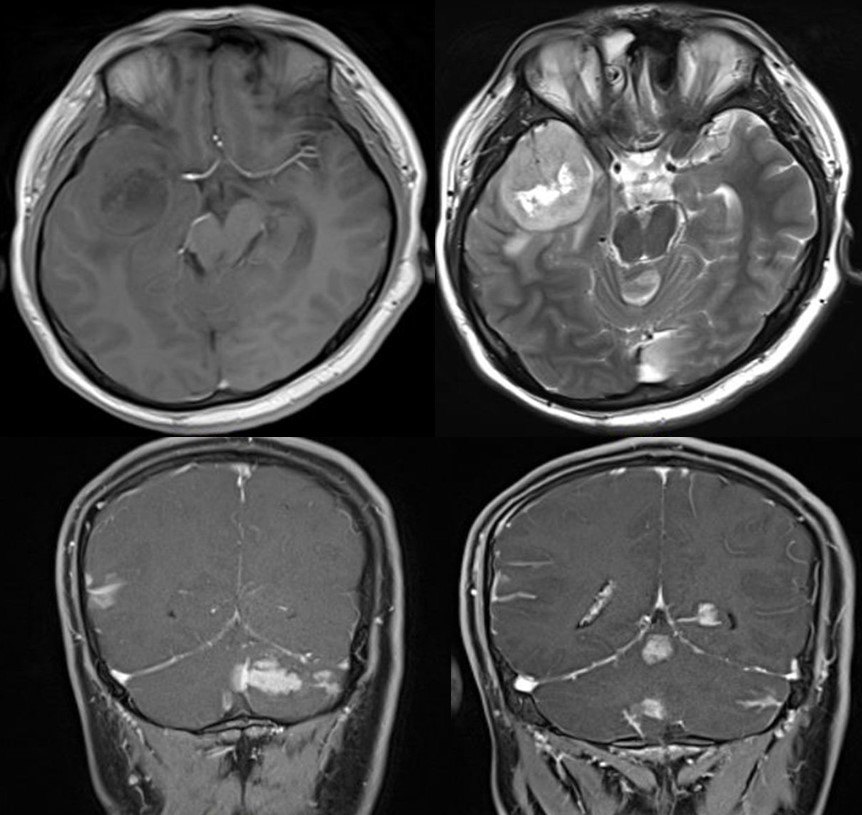

头颅MRI示:左侧颞叶深部天幕上缘病变,T1低信号,T2混杂信号,不均匀强化;左侧丘脑病变,T1等信号,T2高信号,未见明显强化。

术后病理提示:左侧天幕缘:胶质母细胞瘤(WHO IV级,IDH野生型);左侧丘脑:弥漫性胶质瘤(WHO II级)。